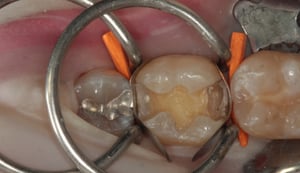

Otturazione in composito a livello di primo molare inferiore destro. Il restauro in amalgama di argento esistente presenta una frattura e viene pertanto sostituito. La rimozione del materiale metallico viene eseguita isolando il dente dal cavo orale mediante diga di gomma. Il dente viene come per ogni procedura sabbiato, mordenzato, trattato con primer ed adesivi ed infine otturato in materiale composito fotopolimerizzabile. La presenza di cuspidi intatte e di spessore sufficiente, conferisce una adeguata resistenza meccanica al restauro eseguito.